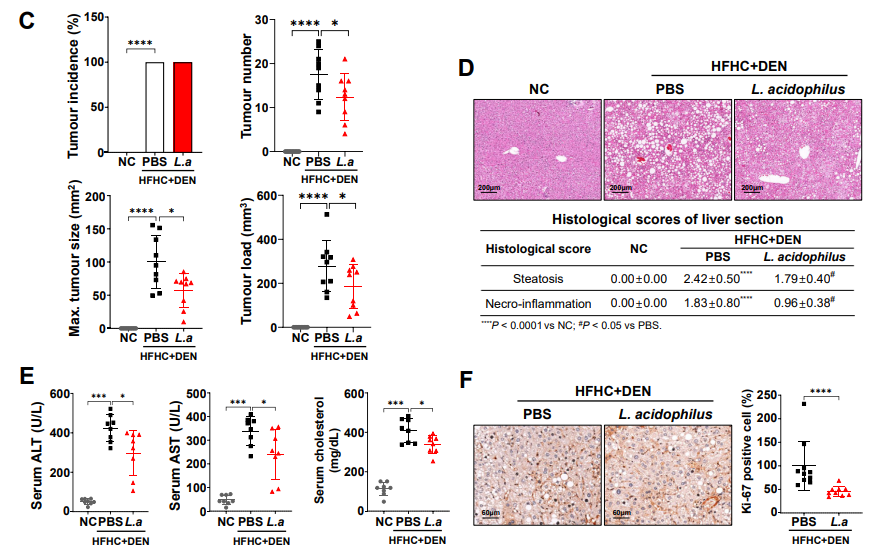

“还有一部分肝癌患者是由脂肪肝发展而来的。” 张华宇说,长久以来,人们都以为肝癌很难治愈,尤其是中晚期,一旦被确诊,感觉是被判了死刑,“实际上,现在对于肝癌的治疗发展很快,有很多手段,除了手术之后,对那些初诊不能手术的患者,还可以采用转化治疗,包括介入治疗,靶向免疫治疗等等,也就是先“保守”治疗,将肿瘤缩小,再寻求手术切除的机会。”